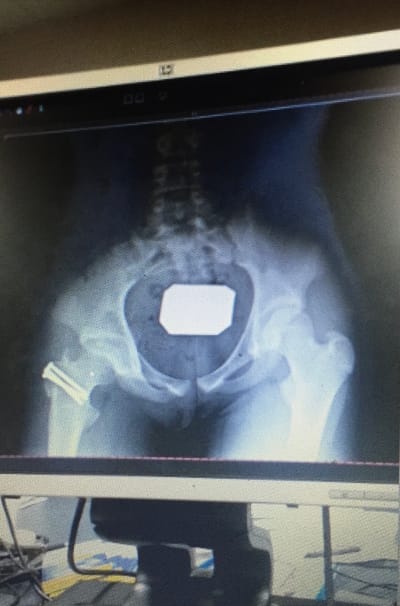

The Story Behind the Scars

This is a part of my life that I mention briefly a lot so I figured it would help if you knew the whole story!